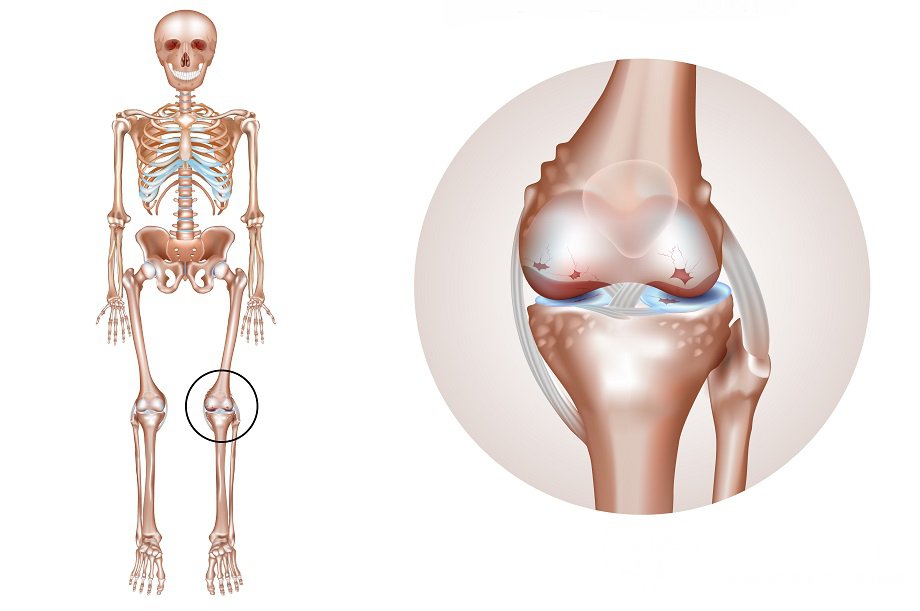

Артрит коленного сустава – распространенное дегенеративное заболевание опорно-двигательного аппаратаДля артрита характерны:

Гонартрит, как любое другое дегенеративное заболевание суставов, развивается вследствие дисбаланса между процессами синтеза и деградации в хрящевой и прилегающей костной тканях, приводящего в итоге к разрушению хряща.

Если в норме процессы новообразования превалируют, то при артритах данное равновесие смещается в сторону нарастания дистрофии и последующей дегенерации тканей. Первоначальные изменения на клеточном уровне приводят к нарушению тканевого гемостаза, видоизменяется тонкая структура хряща коленного сустава (выявляются очаги помутнения, истончения и разволокнения, микротрещины и разрывы). Ввиду происходящих структурных перестроек хрящ теряет эластичность, страдает его амортизационная функция, нарушается взаиморасположение сочленяющихся поверхностей, усугубляя деградацию.

Компенсаторно, в ответ на истончение хрящевой прослойки, начинается уплотнение и разрастание прилегающей костной ткани, формируются костные выросты, шипы, осложняющие адекватное функционирование коленного сустава и усугубляющие течение заболевания.